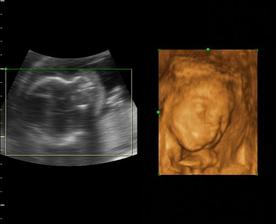

22.12.2007 máme pozitívny test /Mama test/ sme 10 DPO. 3.1.2008 potvrdené tehotenstvo z krvi Hcg 7800. 15.1. UZV, miminko nám krásne rastie sme v 7 tt a už sme dostali aj tehotenský preukaz.

22.augusta 2008 sa náš drobček narodí cisárskym rezom nevieme sa toho dňa dočkať.